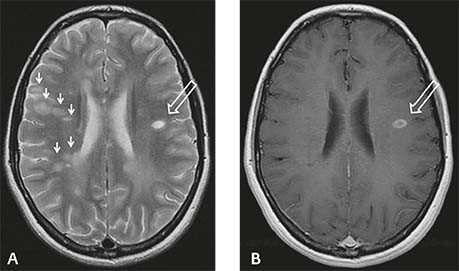

De waarschijnlijkheidsdiagnose MS berust op twee pijlers: spreiding in tijd en plaats van bij MS passende verschijnselen. Dat betekent dat er minimaal twee episodes van uitval moeten zijn geweest, vanuit verschillende lokalisaties in het centrale zenuwstelsel. Bij bovenstaande patiënte, die een goed bij MS passende episode van uitval doormaakt, kan men de diagnose MS dus nog niet stellen: de klachten kunnen zijn ontstaan door één groter wordende laesie. Voor de diagnose is een tweede episode vanuit een ander deel van het centrale zenuwstelsel nodig, die soms snel, maar soms pas na jaren komt. In het laatste geval ontstaat voor patiënten een lange en onzekere periode. De nieuwste diagnostische criteria laten echter toe dat men een tweede episode ook kan vaststellen door nieuwe, asymptomatische laesies aan te tonen bij herhaald MRI-onderzoek van de hersenen en/of het ruggenmerg [figuur 2].5 Hierdoor kan men de diagnose MS vaak veel eerder stellen. Lumbaalpunctie voor onderzoek van de liquor cerebrospinalis is tegenwoordig meestal niet nodig.